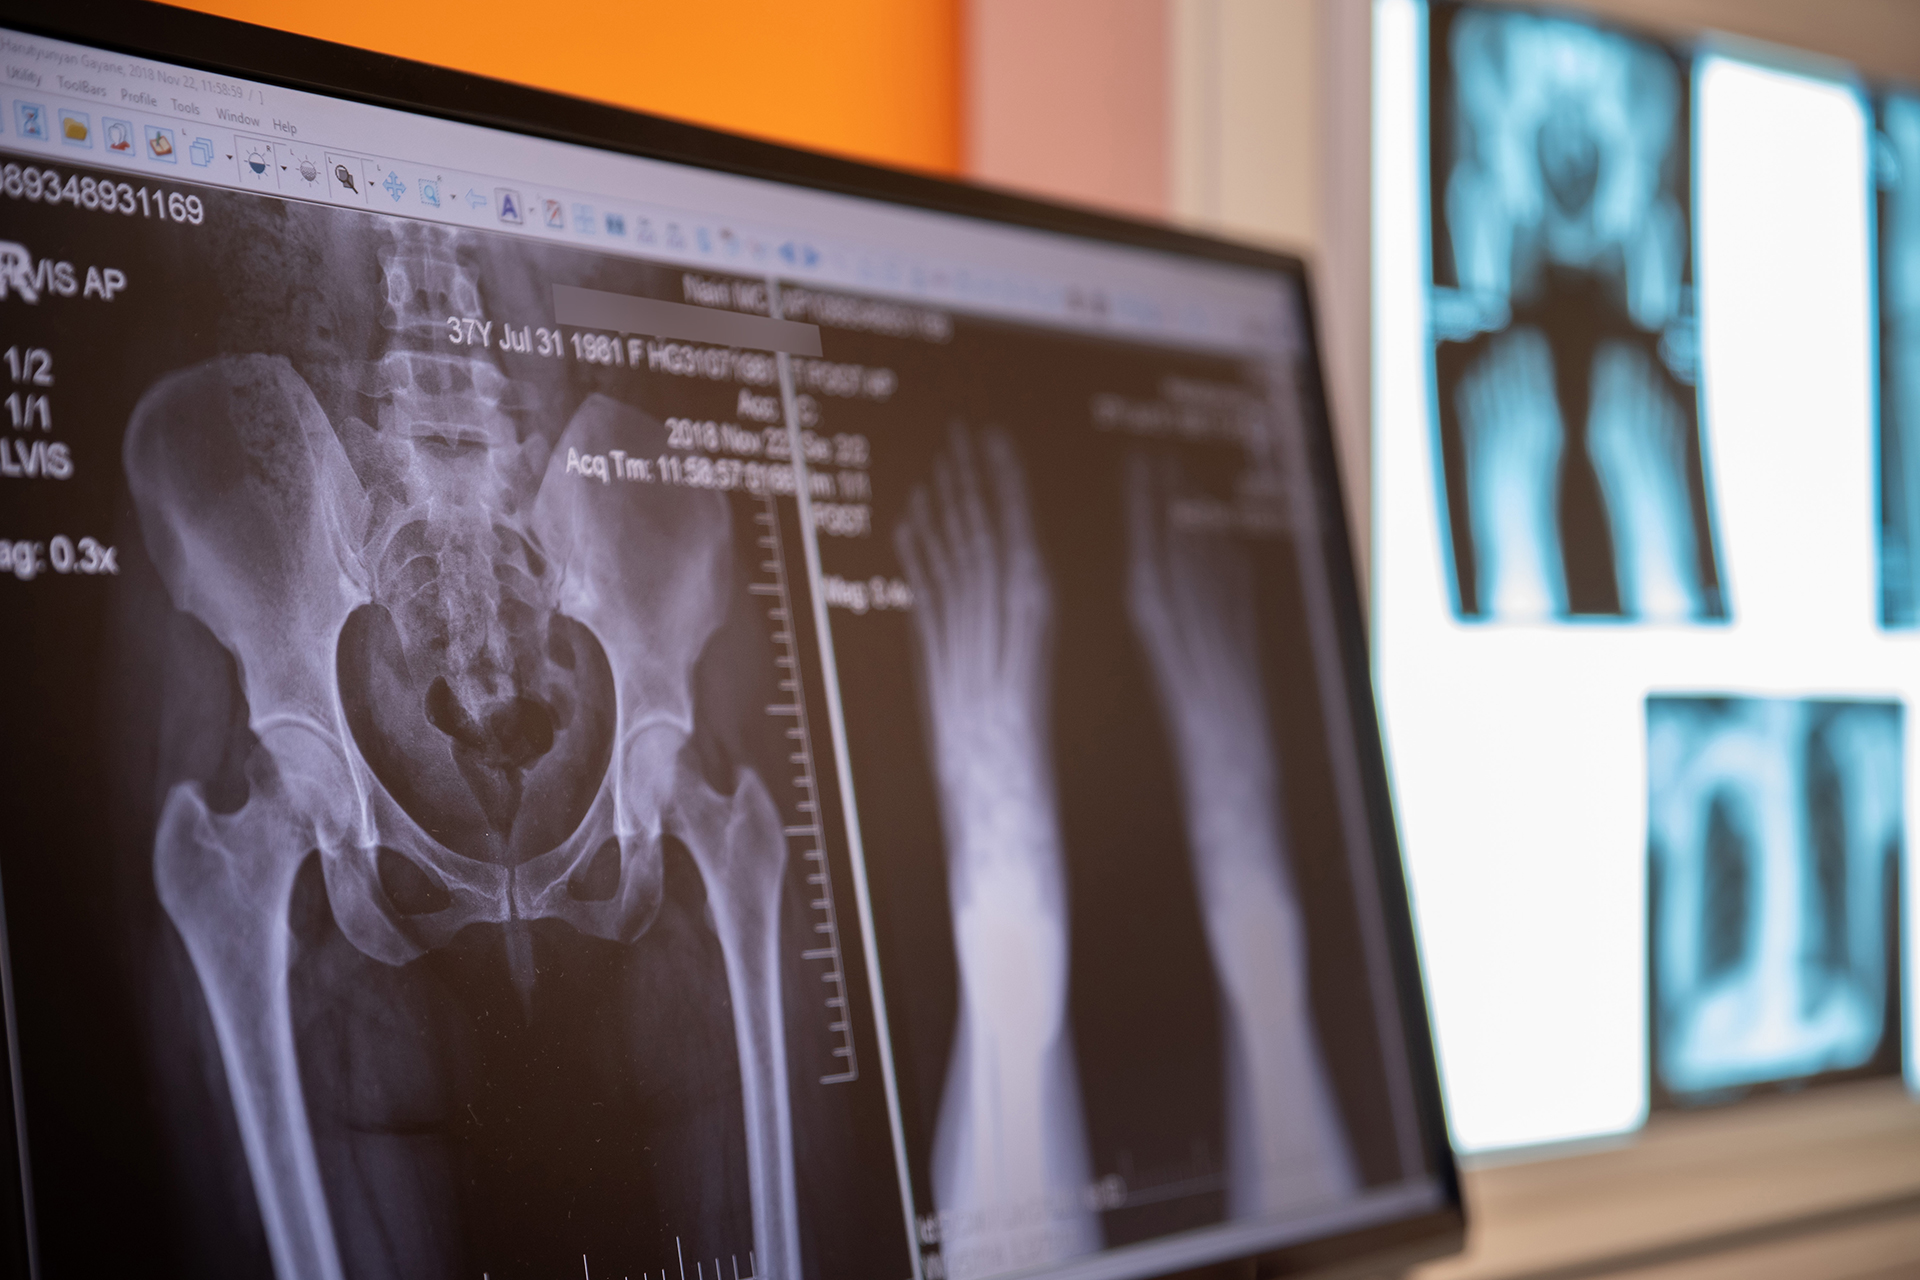

«Նաիրի» բժշկական կենտրոնում ռենտգեն ախտորոշումն իրականացվում է Siemens Luminos Fusion թվային սարքով, որն ապահովում է բարձր ճշգրտությամբ պատկերներ և նվազ ճառագայթային բեռնվածություն։ Ռենտգեն հետազոտությունը կիրառվում է թոքերի, ողնաշարի, հոդերի, ոսկրերի, միզասեռական և աղեստամոքսային համակարգերի ախտաբանությունների դեպքում։ Հատկապես արդյունավետ է վնասվածքների, ցավերի, շնչառական խնդիրների, բորբոքումների կամ ուռուցքային գործընթացների գնահատման համար։ Սարքը թույլ է տալիս անցկացնել հետազոտություն արագ, անվտանգ և հարմարավետ պայմաններում։ Բոլոր հետազոտությունները մեկնաբանվում են փորձառու ռադիոլոգների կողմից՝ ապահովելով ճշգրիտ ախտորոշում։